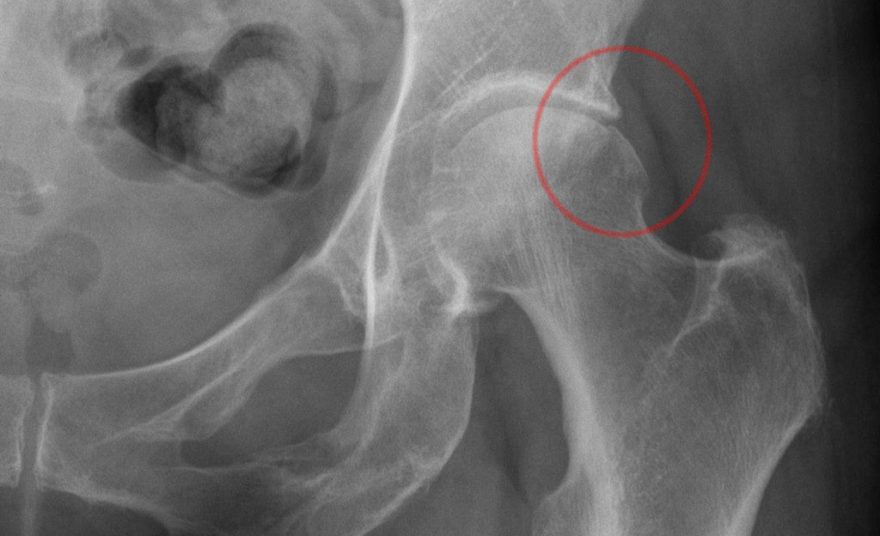

Феморо-ацетабулярный импинджмент: вернуть суставу здоровье и подвижность

Постоянная боль в паху и скованность в тазобедренном суставе мешают жить полной жизнью. Наша статья подробно объясняет причины феморо-ацетабулярного импинджмента, методы его точной диагностики и современные подходы к лечению.

Дисплазия тазобедренного сустава у взрослых: полное руководство по лечению

У вас диагностировали дисплазию тазобедренного сустава и вы ищете понятную информацию о своем состоянии. Эта статья поможет разобраться в причинах, симптомах и всех современных методах лечения от консервативных до хирургических.

Эпифизеолиз головки бедренной кости: понять причину и выбрать лечение

Боль в бедре или колене у подростка может быть признаком эпифизеолиза головки бедренной кости. Наша статья поможет разобраться в причинах, симптомах, современных методах диагностики и вариантах хирургического лечения этого состояния для принятия верного решения.